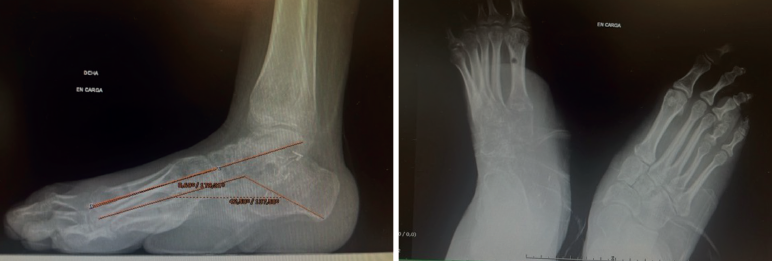

Sus dedos menores se encuentran en ráfaga media y presenta úlceras periódicas en la base de M5 por hiperapoyo (Figura 2). Además, la paciente nunca había tenido un pie plantígrado.

Figura 2. Pie derecho con apoyo en M5 y dedos en ráfaga medial. Radiografía en carga.

Además, se observa una normalización del ángulo de Meary y el de Costa-Bartani (Figura 5).

Figura 5. Radiografías en carga que muestran la normalización de los ángulos de Meary y Costa-Bartani.

El valor normal del ángulo de Meary sería menor de 10° y nos sirve para evaluar la alineación del arco longitudinal medial del pie y cuantificar deformidades sagitales(11).

El valor normal del Costa-Bartani es entre 120 y 130°, y evalúa la altura y la estabilidad del arco medial, y el equilibrio estructural del pie(12).